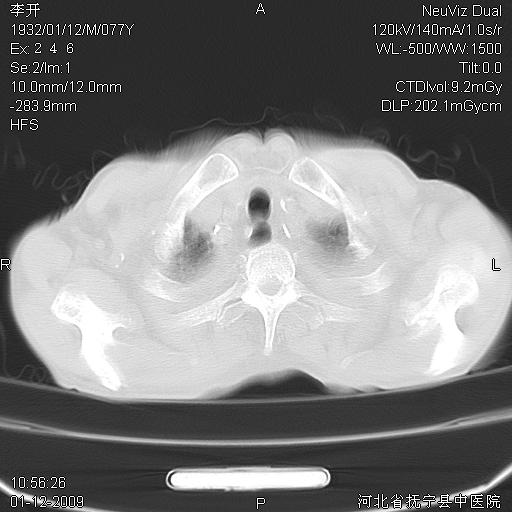

以下是引用黑白光影在2009-1-19 16:49:00的发言:[br]心衰肺水肿;心包、胸腔积液;冠脉钙化;肺部感染。